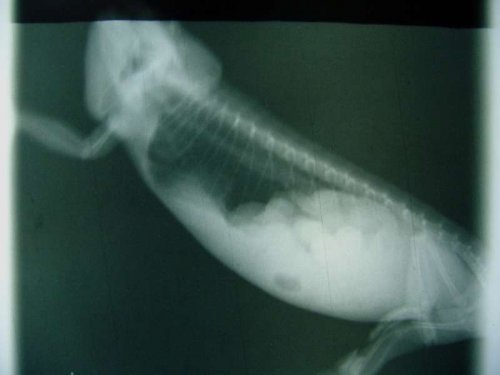

About 4 weeks ago I noticed she was getting even larger than she was and I could feel a hard lump above her hind legs. I took her to the vet and xrays confirmed she was carrying eggs, poorly calcified, unordered, and about full size. I let her go one more week, and another xray. The eggs moved more into lines, and were brighter white. After that xray she was put on calcium glu every other day in hopes to further calcify the eggs and induce contractions. The hard lump I was concerned about never showed in either xray, each time was actually 3 views.

About 4 weeks ago I noticed she was getting even larger than she was and I could feel a hard lump above her hind legs. I took her to the vet and xrays confirmed she was carrying eggs, poorly calcified, unordered, and about full size. I let her go one more week, and another xray. The eggs moved more into lines, and were brighter white. After that xray she was put on calcium glu every other day in hopes to further calcify the eggs and induce contractions. The hard lump I was concerned about never showed in either xray, each time was actually 3 views.